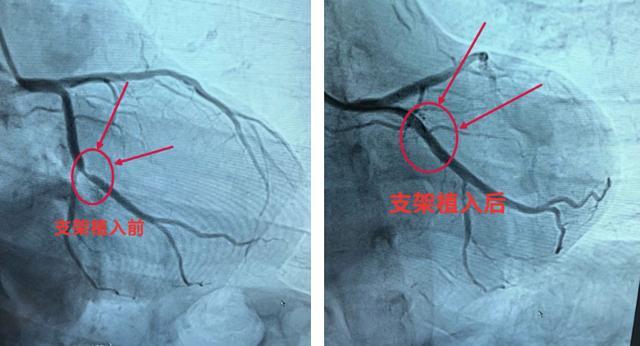

据悉,张女士(化名)因反复胸闷不适2个月,近5天内症状加重,严重影响了日常生活,因此前往永州市零陵区中医医院就诊,入院后经完善冠状动脉造影检查,确诊为冠状动脉回旋支重度狭窄,病情若不及时干预,极易引发急性心肌梗死等严重心血管事件,危及生命。

刘外援主任带领心血管团队详细研判患者病情,与患者及家属充分沟通手术方案、风险及预后,在获得家属同意后,立即为患者实施冠脉支架植入手术。

手术过程顺利,团队精准操作,成功开通狭窄血管,恢复心脏正常供血。